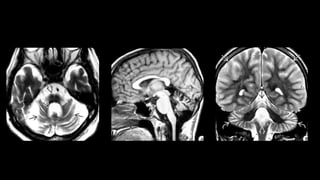

Ataxia espinocerebelar

• Grupo de desordens clinicamente e geneticamente heterogêneo

• Mais de 60 tipos

• Herdada e progressiva

• Subdivisão

• Autossômicas recessivas

• Friedreich ataxia

• Autossômicas dominantes

• Adultos

• Distúrbios de macha, movimento ocular, mácula